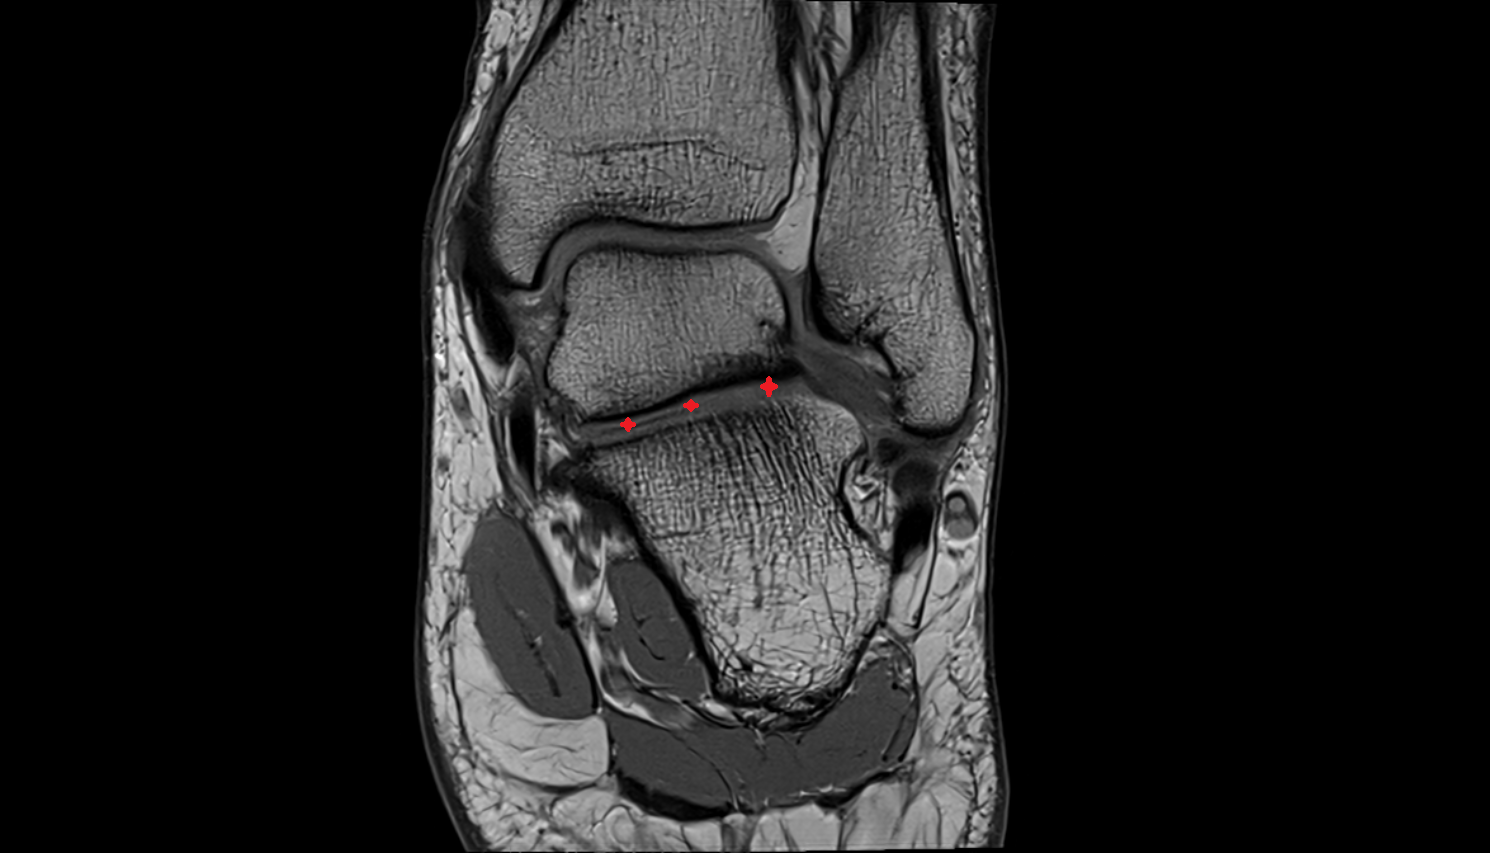

- Ankle joint

- Talocalcaneal joint

- Talocalcaneonavicular joint

- Anterior talofibular ligament

- Posterior talofibular ligament

- Deltoid ligament complex

- Talocalcaneal interosseous ligament